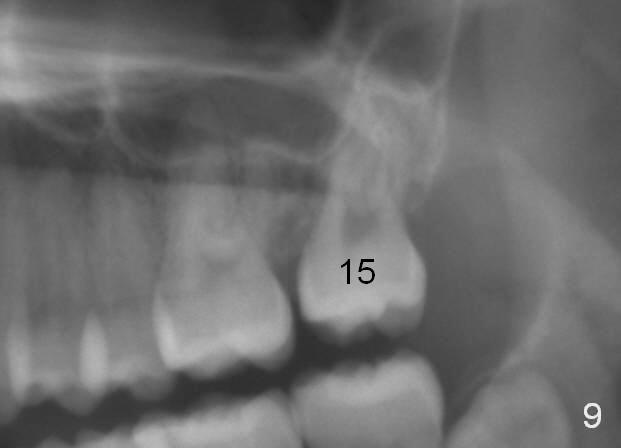

The distobuccal cusp of the tooth is subgingival 8 months post banding (Fig.6 (mirror view) *). A 2nd surgery is performed to expose the gold chain (Fig.7 <) and a bracket is placed. With arch wires, eruption of the impacted tooth is quickened (Fig.8). Later a 3rd minor surgery is done to place a lingual button to facilitate lingual cusp eruption. Finally a band has to be placed at #15. Treatment finishes in 2 years. The patient (15 years 2 months old) returns for follow up 3 months post debanding (Fig.9). There is no bone loss around the tooth #15 2 years 4 months post de-banding (Fig.11, as compared to the tooth #2 (Fig.10)).